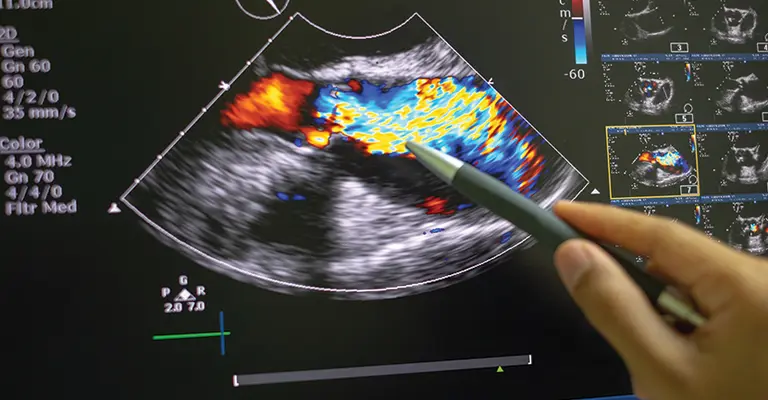

Join Dr. Joel Furda as he presents a live demonstration of the technique of echocardiography, including discussion of what is normal versus various states of disease. Echocardiography is an essential part of accurate and timely diagnosis of many cardiac abnormalities.